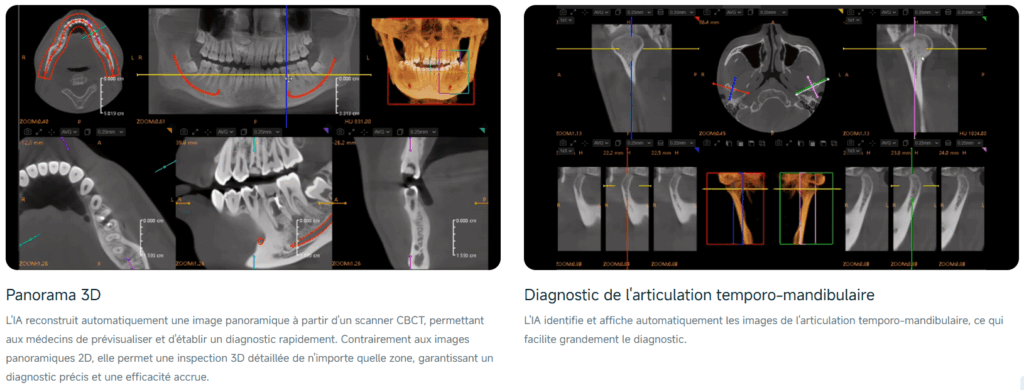

Votre puissant assistant IA